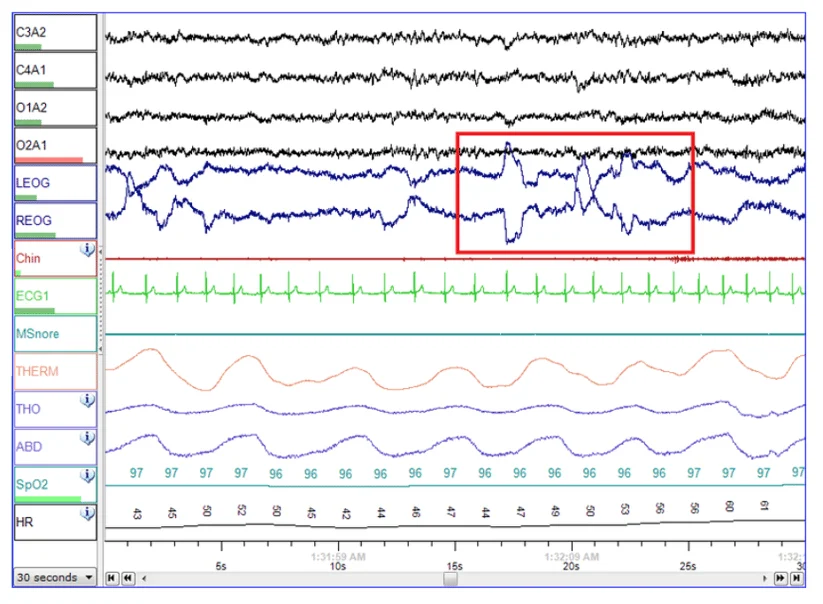

현재까지 우리의 잠에 대해 가장 정확하게 알 수 있는 방법은 수면 전문 의료기관에서 진행하는 수면다원검사(PSG, 이하 PSG)입니다. 수면 전문 의료기관에서 전문가의 감독 하에 얼굴과 두피, 손가락, 코 등에 센서를 붙이고 하룻밤을 자며 뇌파, 혈중 산소포화도, 호흡 등을 측정합니다. 또한 근전도 검사, 안전도 검사, 심전도 검사 등을 통해 수면의 단계별 상태와 코골이, 수면 무호흡증, 기면증 여부, 뒤척임, 깸 등을 파악할 수 있습니다. 검사를 위해서는 반드시 병원에 가야 하고, 적지 않은 비용이 소요되며, 결과지에 대한 전문가의 해석을 통해서만 나의 수면 데이터를 파악할 수 있어서 반복적이고 일상적인 검사가 거의 불가능하죠.

전문가의 판독이 없이는 해석이 거의 불가능한 PSG 검사지